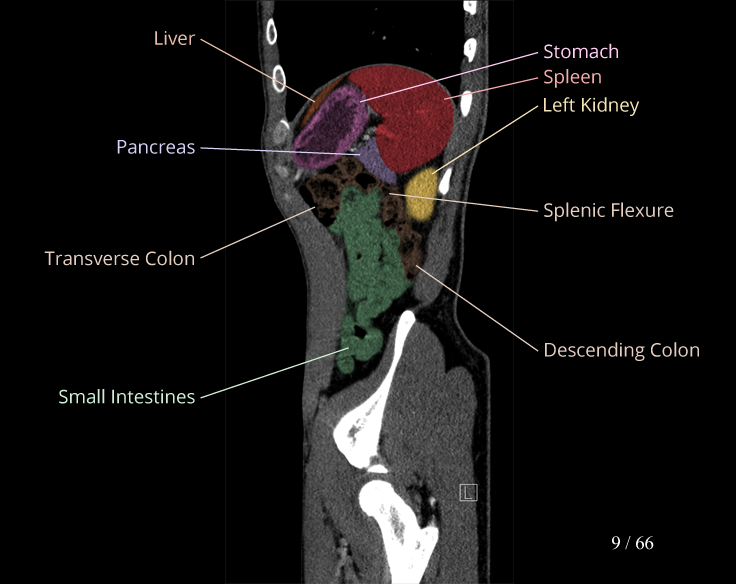

Body

Covers abdominal CT anatomy.